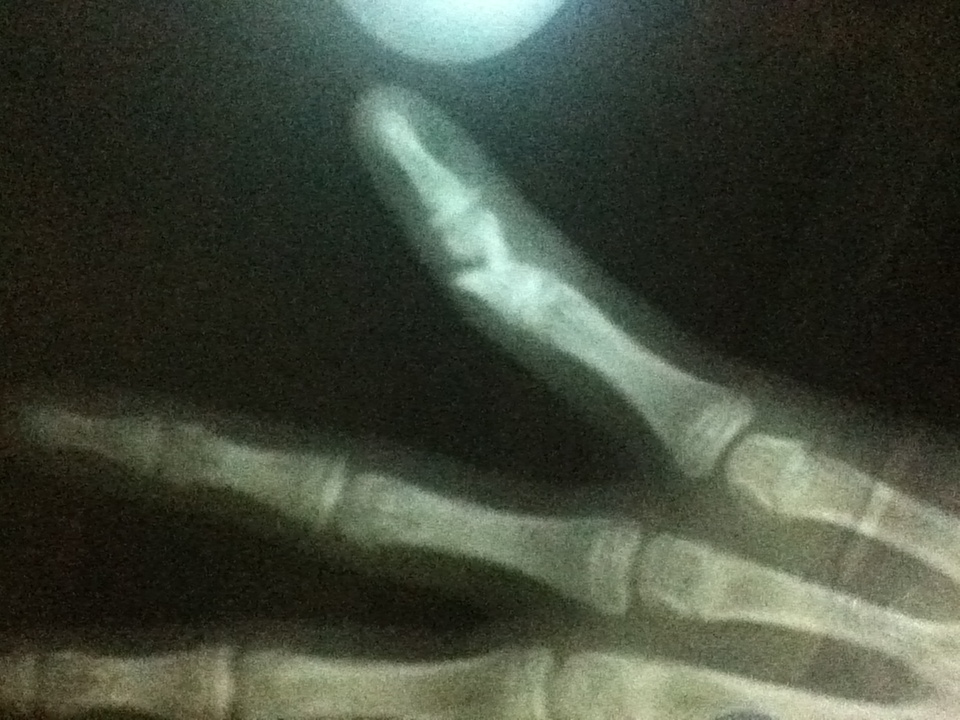

月曜日に小指の針金を抜いた息子1は、手術した病院から「最初に見てもらった病院でリハビリしてねー」と紹介状を持って最初に行った病院に翌日出向いた。

が、言われたのは「昨日針金抜いて、今日からリハビリは怖くて出来ない。シーネ(支えの板みたいなやつ)もしないでいるのは危ないと思うんだけど、執刀医はどう行ってるの?骨はくっついてるわけないよね?手術の状況が分からないから何とも言えないんだけど、リハビリ中にまた骨ずれましたって言われても困るし、しばらくの間は向こうに戻って経過見てもらって。あと、固定もきちんと聞いてきなさい。」

したらね、「うちでは必要無いと思ったから固定してないし、若いから治りは早いだろうし、動かさないと固まっちゃうだろうし、、、あちらの先生は慎重なんだね、、、」という事で、結局「学校にいる間は固定して、家に戻ったら外してリハビリしてね(ぬそが使ってたリハビリボールがある)」と言われて参りましたとさ。

明日、息子1の指から針金が抜かれます。

プールの見学を一緒にしていた同級生も過去にちがう指だけど経験したことがあるらしく、「麻酔無しだぞー!いきなり抜かれるぞー!ごりごりイタイぞー」と脅かしまくってるらしくww

息子1、明日10:30から手術やってさ。